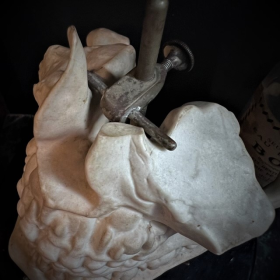

There is a small lack at the nasal level, when viewed from the front on the right side.

What is original is that the whole piece is made of unglazed porcelain, which is called biscuit, except for the teeth which are well glazed.

Original metal fixation system